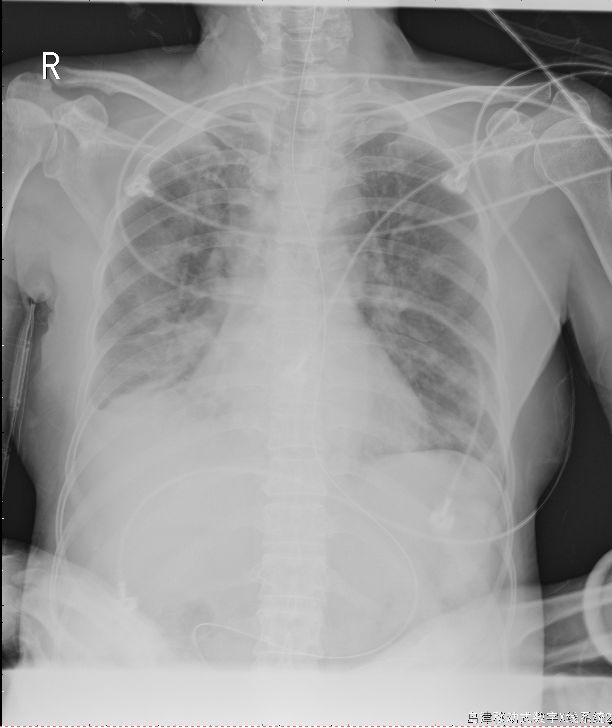

图16-1 复查胸片病灶较前增多

诊疗经过